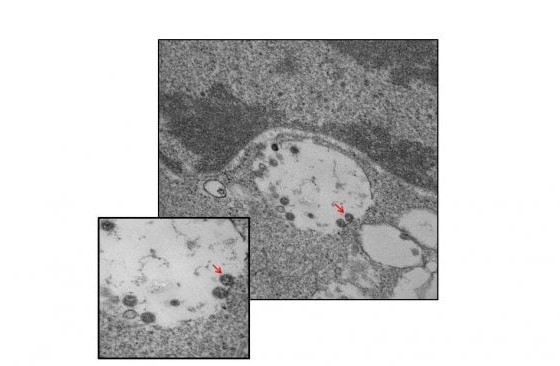

Το εργαστήριο των μολυσματικών ασθενειών του νοσοκομείου Sacco στο Μιλάνο έδωσε τις πρώτες εικόνες στις οποίες φαίνεται ο κορωνοϊός μέσα από ηλεκτρονικό μικροσκόπιο. Ο ιός απομονώθηκε από συγκεκριμένη ιατρική ομάδα υπό τους καθηγητές Massimo Galli και Gianguglielmo Zehender σε συνεργασία με το Τμήμα Παθολογικής Ανατομίας, αλλά και την καθηγήτρια Manuela Nebuloni του Τμήματος Βιοϊατρικών και Κλινικών Επιστημών Luigi Sacco. Η ανακοίνωση έγινε από το κρατικό πανεπιστήμιο του Μιλάνου.

Στη φωτογραφία, σε μεγέθυνση παρατηρούνται τα ιικά σωματίδια του SARS-CoV-2 (υποδεικνύονται με βέλη), τα οποία συνδέονται με τις μεμβράνες στην επιφάνεια και εντός των κυττάρων VERO E6, που χρησιμοποιούνται για απομόνωση.